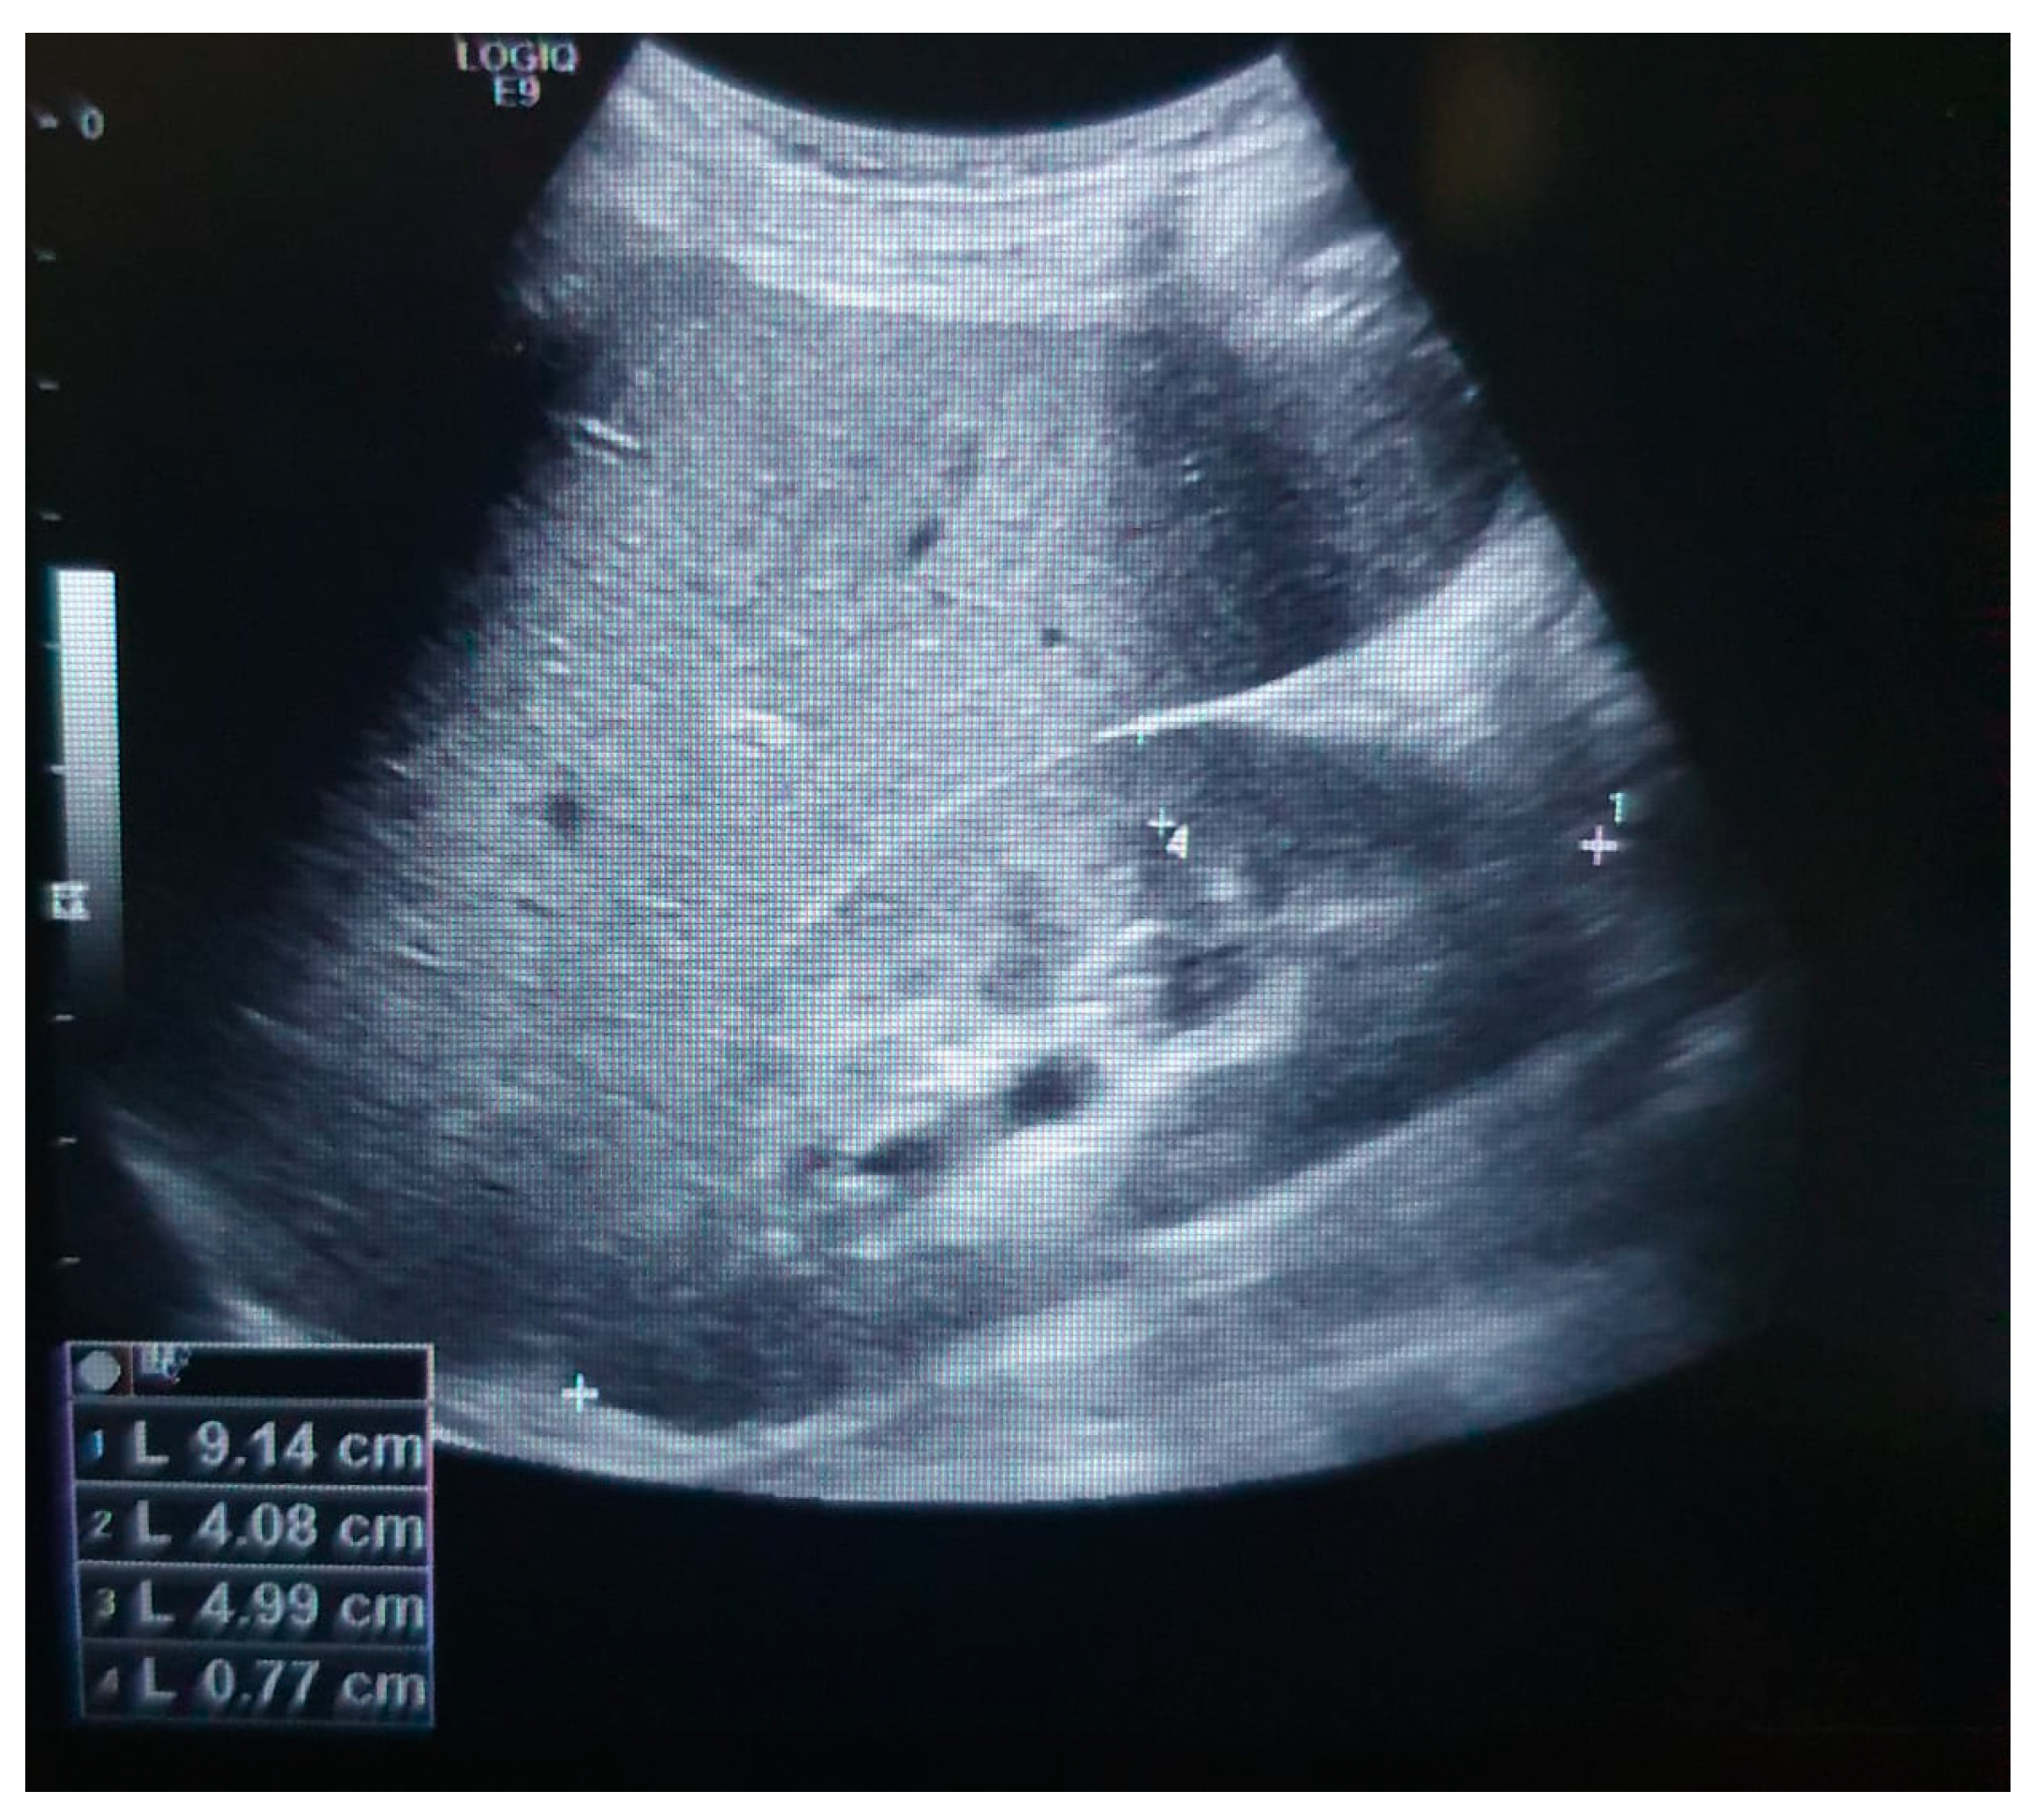

2. Detailed Case Description